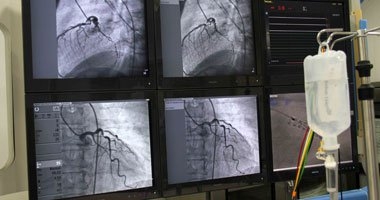

بعد التقدم فى قساطر القلب، فإن إدخال الدعامات إلى الشرايين التاجية عن طريق الشرايين دون الحاجة إلى جراحة أصبح إجراءً شبه روتينى، لكن قد تحدث معه بعض المضاعفات. ففى 6:2% من الحالات تحدث بعض مضاعفات النزف نتيجة استخدام عقاقير السيولة فى موقع إدخال القسطرة، وهذا قد يؤدى فى بعض الأحيان إلى الموت إن كان كثيرا. لكن وفقا لموقع ميديكال نيوز توداى تمكن الباحثون فى معهد القلب التابع لمؤسسة مينيابوليس فى ولاية منيسوتا فى الولايات المتحدة الأمريكية من تطوير أداة تحليلية بسيطة لتوضيح مدى نسبة تعرض المريض للنزيف وخطر تعرضه له، مما يحسن من نتائج القسطرة القلبية. وذكر الموقع أن استخدام هذه الأداة التحليلية مكنت الأطباء خلال الشهر الماضى فى المعهد من تقليل كل مضاعفات ما بعد العملية بنسبة 5.3% تقريبا بما فيها نقل الدم، وتشمل الأداة التحليلية استخدام بيانات المريض وتاريخه المرضى لدى السجل الوطنى لبيانات القلب والأوعية الدموية فى حساب مدى تعرضه للخطر هل هو عال أو متوسط أو منخفض، وبناءً عليها يتم أخذ الاحتياطات اللازمة.